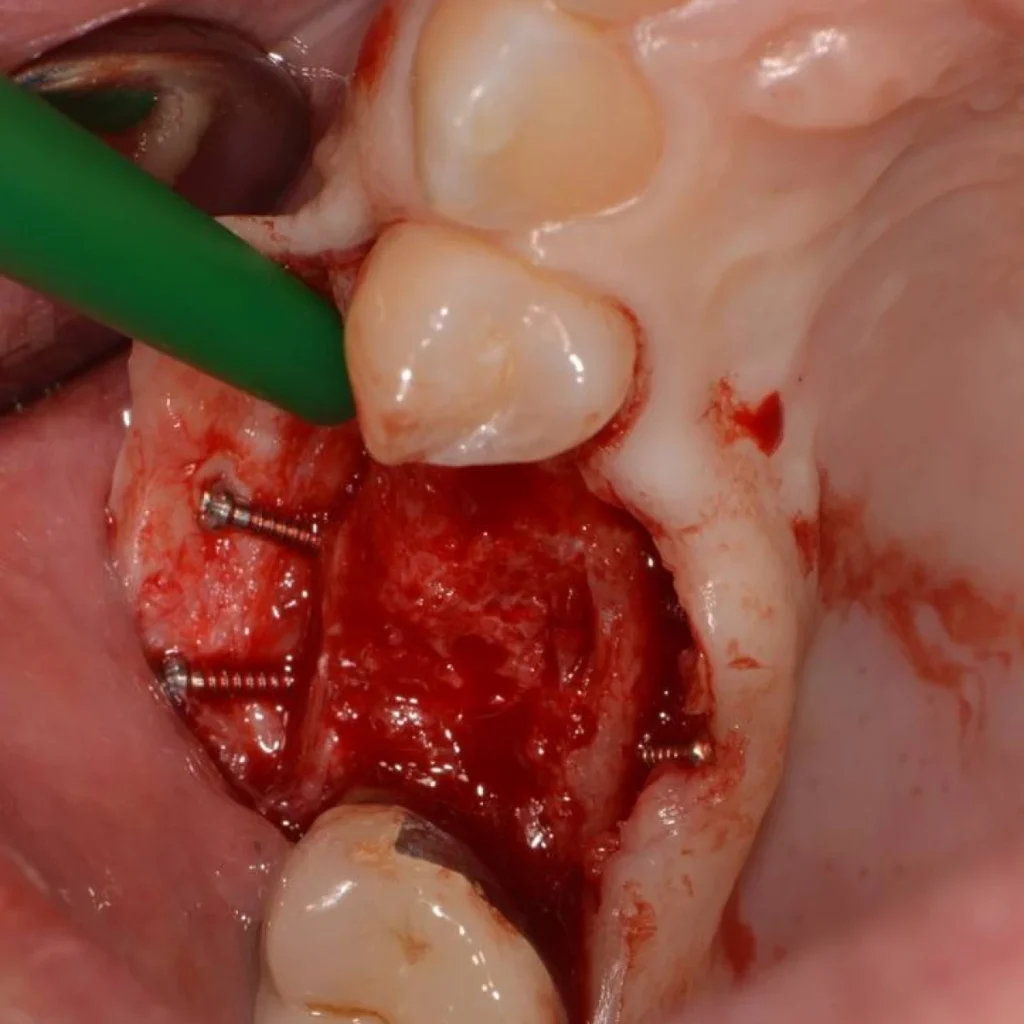

- Après discussion avec la patiente, il est décidé d’effectuer une greffe autogène, véritable « gold standard » dans ce genre de situation.

- L’intervention est réalisée sous anesthésie locale.

- Il s’agit de prélever un greffon osseux dans la zone postérieure de la machoire inférieure de la patiente. Ce greffon est ensuite modelé et transfixé avec des vis au niveau du site à traiter.

- La gencive est ensuite refermée avec des sutures.